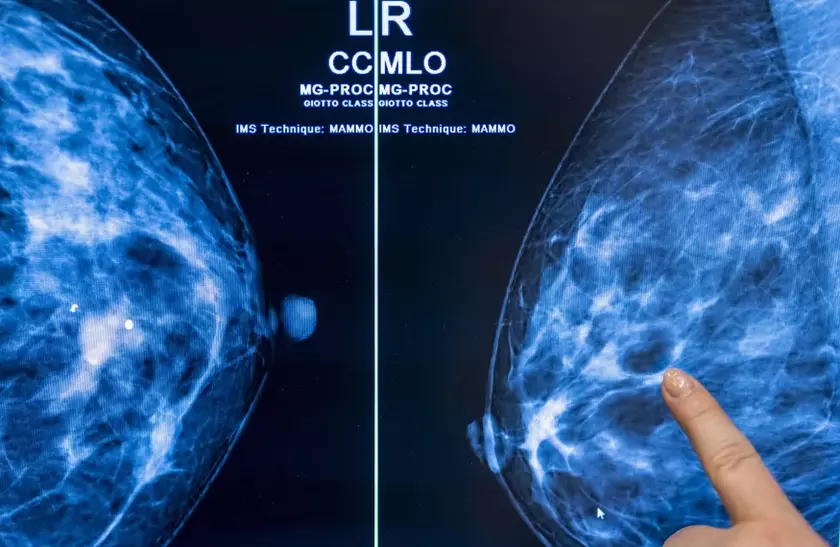

Использование искусственного интеллекта в маммографическом скрининге рака может безопасно сократить нагрузку на радиолога почти в два раза без риска увеличения числа ложноположительных результатов.

Исследование, проведенное группой ученых Лундского университета (Швеция), включало наблюдение за 80 033 женщинами в течение чуть более одного года. Из 39 996 пациенток, которым в случайном порядке были назначены скрининги рака молочной железы с использованием ИИ, у 28% выявили раковые опухоли.

Из остальных 40 024 пациенток, прошедших традиционное обследование, рак был выявлен только в 25% случаев.

Частота ложноположительных результатов как при использовании ИИ, так и при обычном скрининге составила 1,5%. Что особенно важно, радиологам, работающим с ИИ, пришлось просмотреть на 36 886 скринингов меньше, чем их коллегам. Это на 44% сократило их рабочую нагрузку.

"Маммографический скрининг с поддержкой ИИ привел к аналогичному показателю выявления рака по сравнению со стандартным двойным считыванием, при этом нагрузка на считывание была существенно ниже, что свидетельствует о безопасности использования ИИ в маммографическом скрининге", — говорится в заключении исследования.